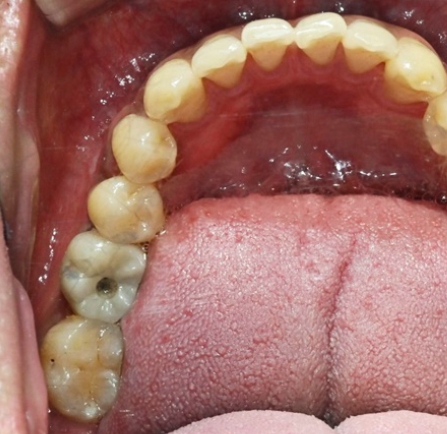

< Some implant surgery cases >

Treatment period: 24.11.3 - 24.12.3

Problem tooth location: tooth no. 46